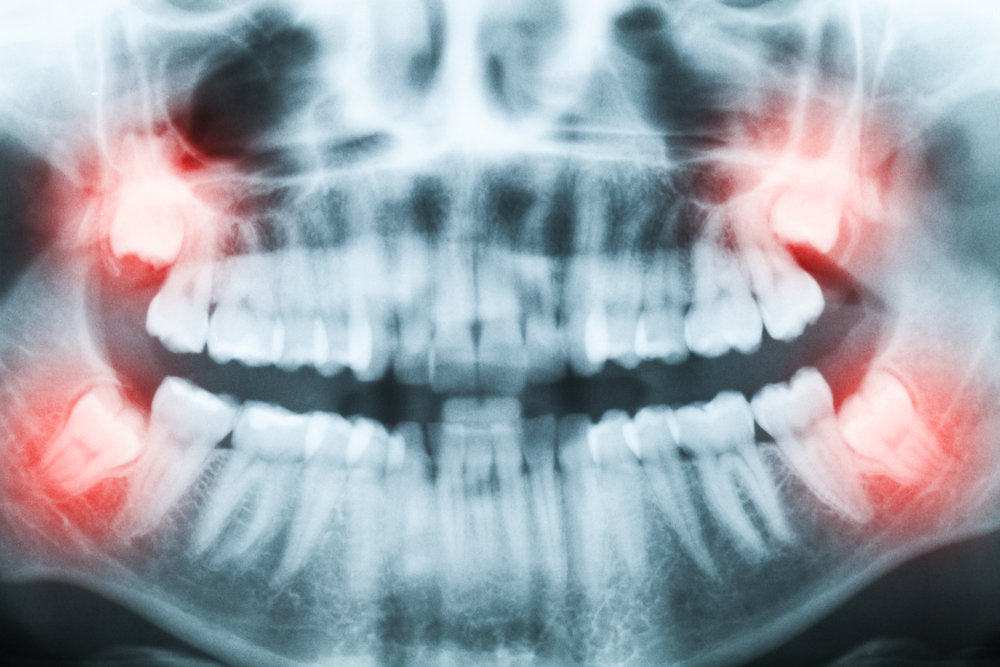

Sebbene molti denti del giudizio emergano senza complicazioni, esistono segnali che indicano la necessità di una valutazione professionale. Dolori persistenti, difficoltà a aprire completamente la bocca, infiammazioni ricorrenti o mal posizionamento dei denti vicini possono richiedere un intervento. La valutazione da parte di un dentista, spesso supportata da radiografie, permette di capire se i denti stanno seguendo un percorso corretto o se il loro posizionamento può creare problemi a lungo termine.